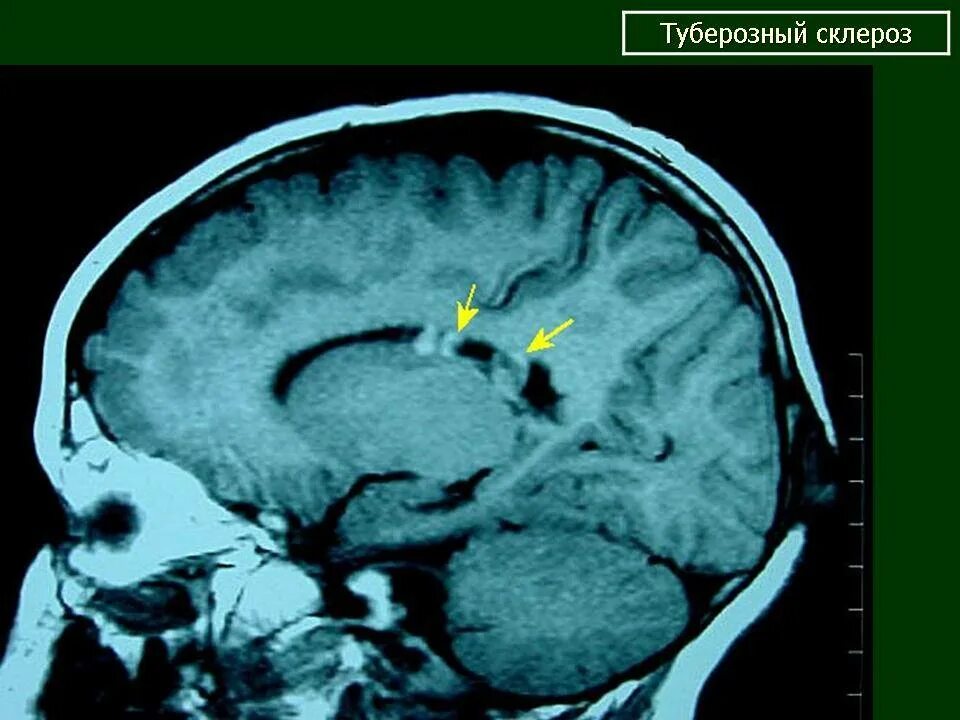

Туберкулезный склероз